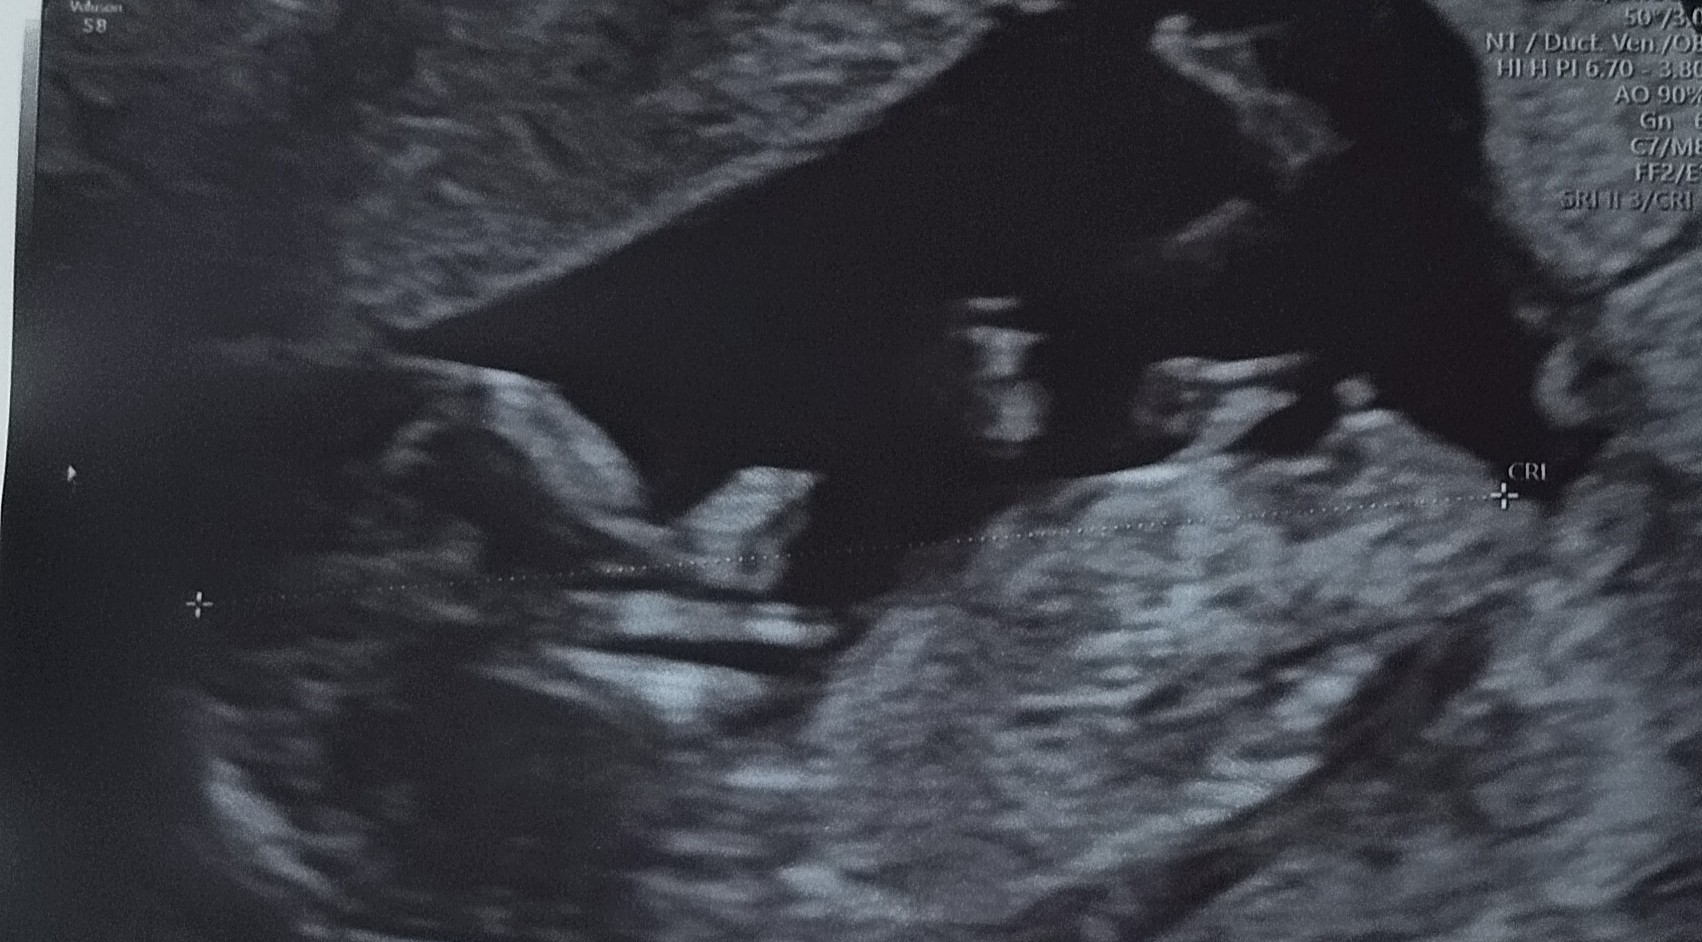

Cześć! Jak wy uważacie bardziej chłopak czy dziewczyna? Może wszystko się jeszcze zmienić ? Za wcześnie na określenie płci ?

Pan doktor dał znak zapytania, niby dla niego chłopak tak na 85% .